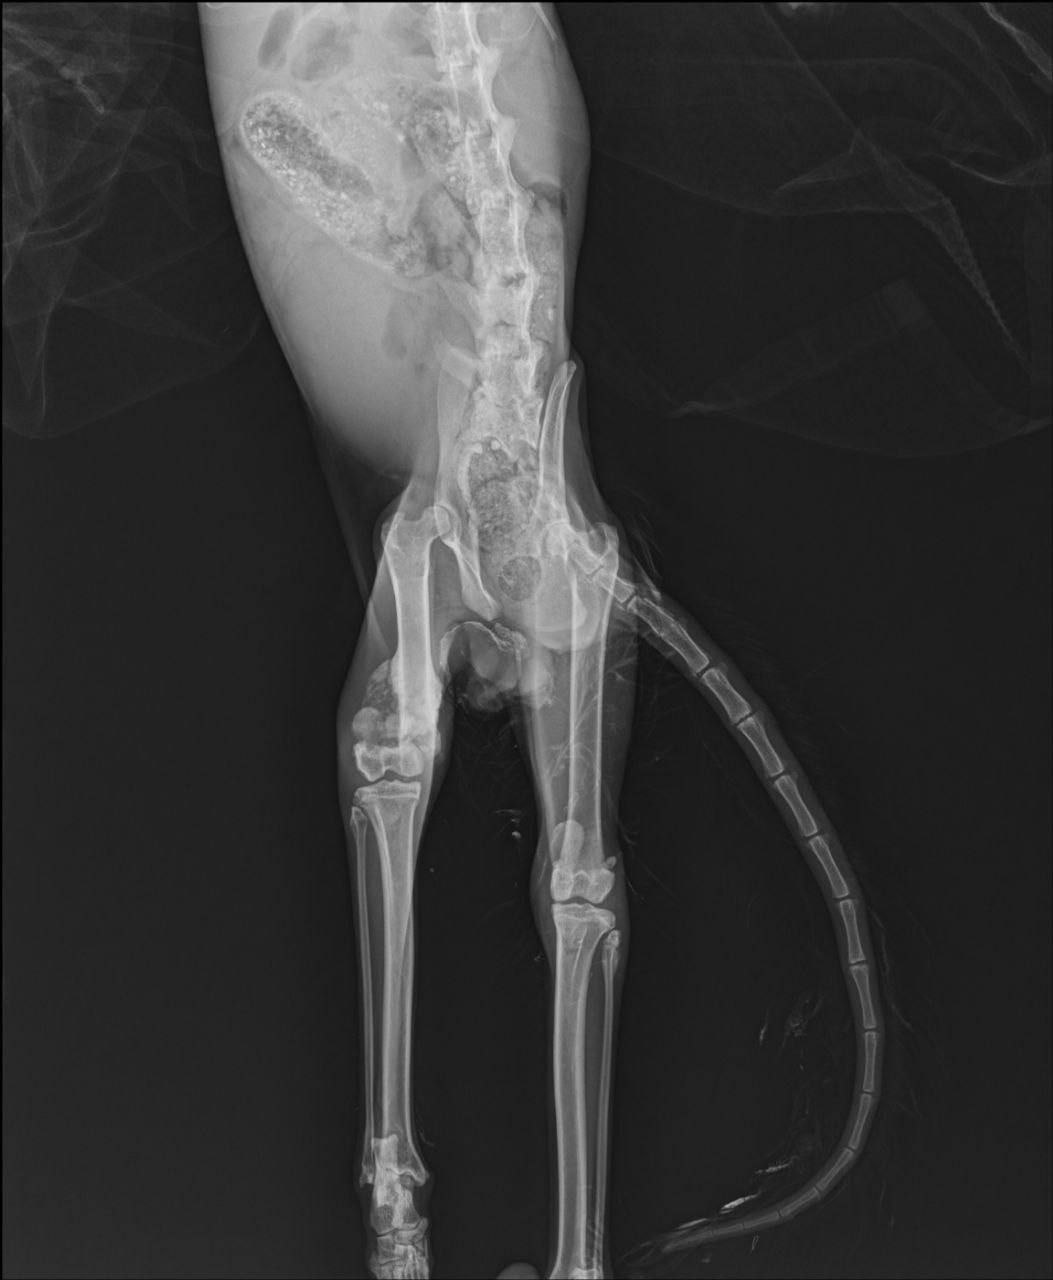

Котика отвезли в Ларнаку в клинику. Под крыло взяла Виленочка, за что ей сердечная благодарность. У котика тяжелейшие переломы, повреждение нерва... Завтра будет более полный апдейт от автора поста, замечательной девушки, которая не прошла мимо, а начала срочно искать помощь. Будет открыт сбор на реквизиты Вилены, очень нужна будет ваша поддержка, ребята 🥰

По состоянию котика Анна уже написала вкратце выше, если кому-то интересны детали - прикладываю видео, с описанием травм от доктора, снято с его разрешения. Боюсь, корректно перевести на русский я не смогу, поэтому кому интересна эта информацию, посмотрите пожалуйста видео.

Да, все верно. Но хочу пояснить, что это было не ультимативном формате, а «если спросите меня, то я бы…». И пока котику делали рентген мне уже предложили помощь Анна и Вилена, мне нужно было только отвезти кота в Ларнаку, к врачу Вилены. Поэтому на момент финального заключения я уже приняла решение принять помощь волонтеров.

Какой кошмар((( Получается одну лапу надо ампутировать, а со второй как будет? Говорит, неврологию уже не восстановить 😢